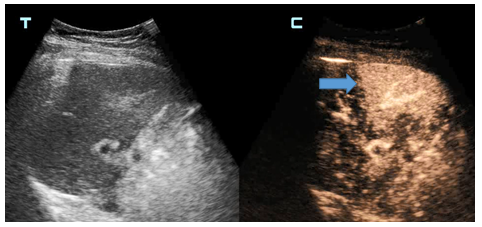

李先生今年45岁,因腹部胀满、疼痛长达一个月,来到德州市第二人民医院就诊。经核磁检查发现,肝右叶有结节,门诊建议进一步检查或穿刺活检明确诊断。随后,李先生做了常规超声检查,但未显示出肝内结节,医生建议行超声造影引导下穿刺活检。在征得李先生同意后,超声医学科主任石洪柱为李先生做了肝脏超声造影,检查历时10分钟,过程中无不适反应。通过超声造影检查发现了肝脏结节,符合恶性肿瘤表现,在超声造影引导下行结节穿刺活检术,最终为李先生明确诊断为肝细胞癌。

石洪柱介绍,超声造影可在常规超声检查的基础上,通过静脉注射超声造影剂,来增强人体的血流散射信号,实时动态地观察组织的微血管灌注信息,以提高病变的检出率,并对病变的良恶性进行鉴别,是一项新型无创的医学影像学技术,被誉为超声发展史上的“第三次革命”。

德州市第二人民医院超声医学科采用的是目前国际上最先进的肝脏超声造影剂——注射用全氟丁烷微球,进行肝脏超声造影检查和引导下穿刺。注射用全氟丁烷微球是针对肝内巨噬细胞特点及肝肿瘤的血液供应特点研制的造影剂,在肝脏肿瘤诊断与鉴别诊断方面有独特的效果,被业界称为“独特肝脏超声造影”。